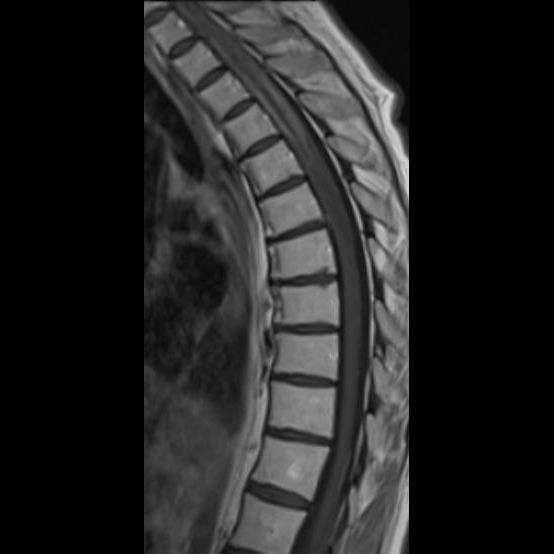

- (A) Torakal MRG’de sagital görüntülerde üst-orta torakal düzeyde T2A hiperintens (oklar), T1A izo-hipointens (ok) uzun segment ekspansil sinyal değişikliği izlenmekte olup sagital postkontrast T1A’da kontrast tutulumu mevcuttur (oklar). Bulgular longitudinal ekstensif transvers miyelit (LETM) ile uyumludur.

- Transvers miyelit sıklıkla santral gri cevheri etkileyen ve üç veya daha fazla vertebral gövde uzunluğunu etkilemektedir (LETM).

- Olgularının %15’i MS’e benzer şekilde kısa transvers miyelit ile karşımıza çıkabilir.

- Omurilik atrofisi ve ekspansiyon/ödem MS’e göre daha fazla görülür.

- Kontrast madde enjeksiyonu sonrasında neredeyse tüm akut NMO lezyonları, yamalı, düzensiz veya periferik olarak kontrastlanma gösterir.